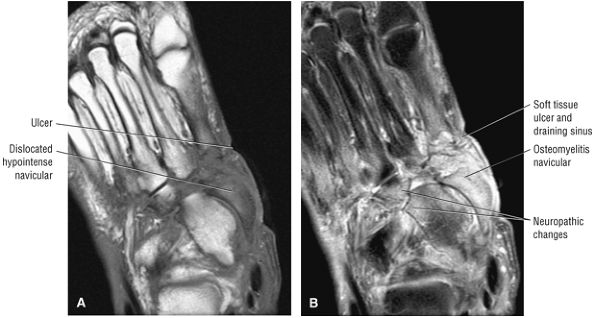

Thickening (Fig. 5.180) or absence of the ligament in acute injury

-

Subacute to chronic residual thickening in a healed and scarred ligament (Fig. 5.181)

Chronic instability associated with attenuated or hypoplastic ligament with sharper, more defined ligament margins